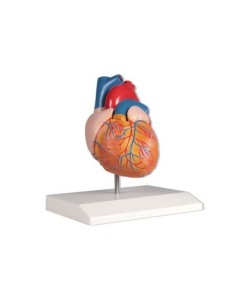

Dal cranio in 22 parti con incastri magnetici ai modelli di colonna vertebrale, da quelli di articolazioni a quelli di cuore, ogni pezzo della nostra collezione è progettato per un’immersione totale nello studio dell’anatomia umana. I nostri modelli, realizzati tramite scansioni di ossa vere, garantiscono un’esperienza tattile autentica e una fedeltà di peso quasi identica agli originali.

Essenziali per studenti e professionisti, i nostri modelli anatomici sono strumenti didattici che permettono di osservare le strutture anatomiche con precisione, eliminando la necessità di dissezioni o studi invasivi. Sono inoltre utili per spiegare ai pazienti le patologie, rendendo la comunicazione più efficace e risparmiando tempo prezioso.